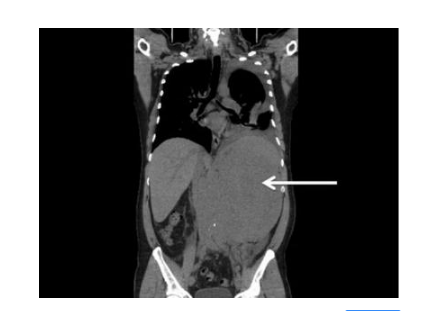

多普勒血流顯像儀檢查

精索靜脈曲張圖片